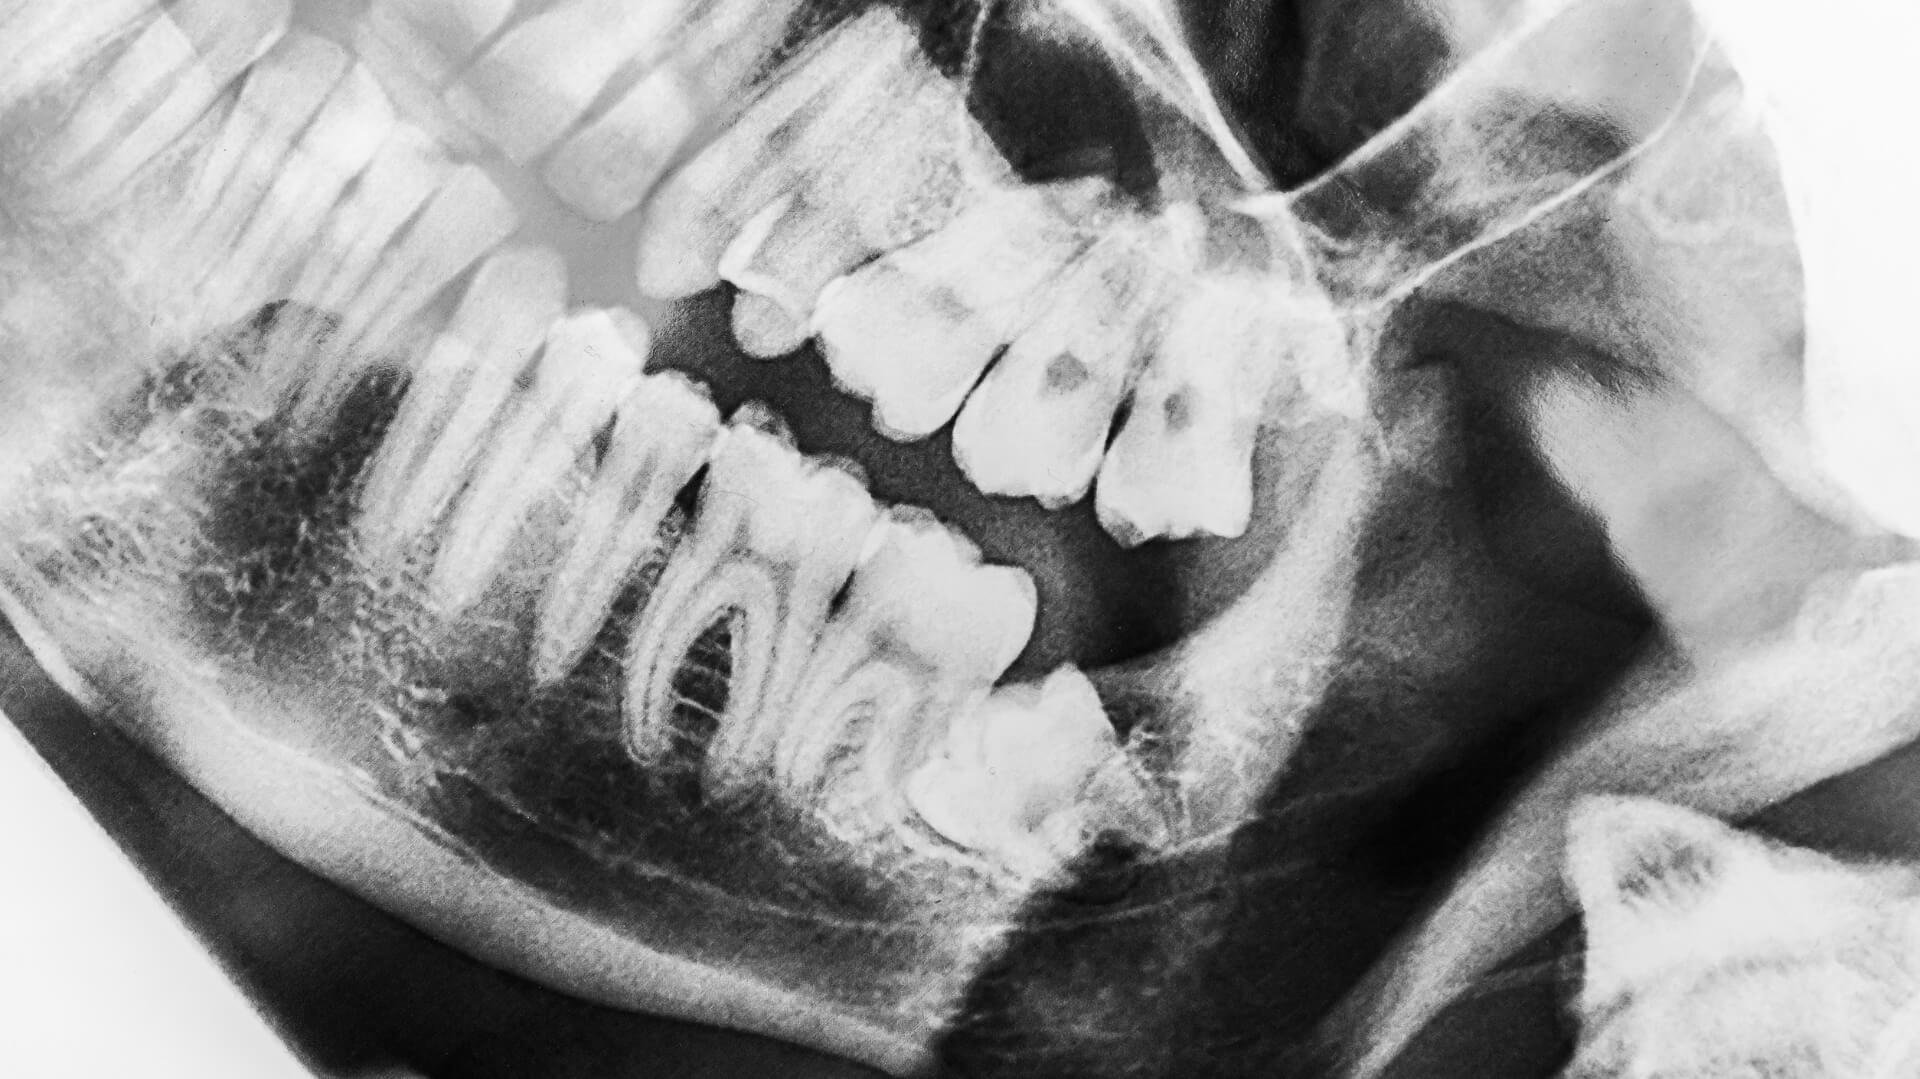

The first step is to take x-rays to better see the entire wisdom tooth and plan the surgery accordingly.

If the wisdom tooth is fully buried then the dental surgeon will need to make an incision in the gums and then remove some bone that lies over the tooth. To minimise the amount of bone that has to be removed in order to get the tooth out, the dental surgeon will often separate the wisdom tooth into smaller pieces. Each piece can then be removed through a smaller opening in the bone.

Wisdom teeth in your upper jaw are generally easier to remove than those in your lower jaw. That's because lower wisdom teeth are more likely to be impacted. The exact degree of difficulty depends on the position and shape of the roots.